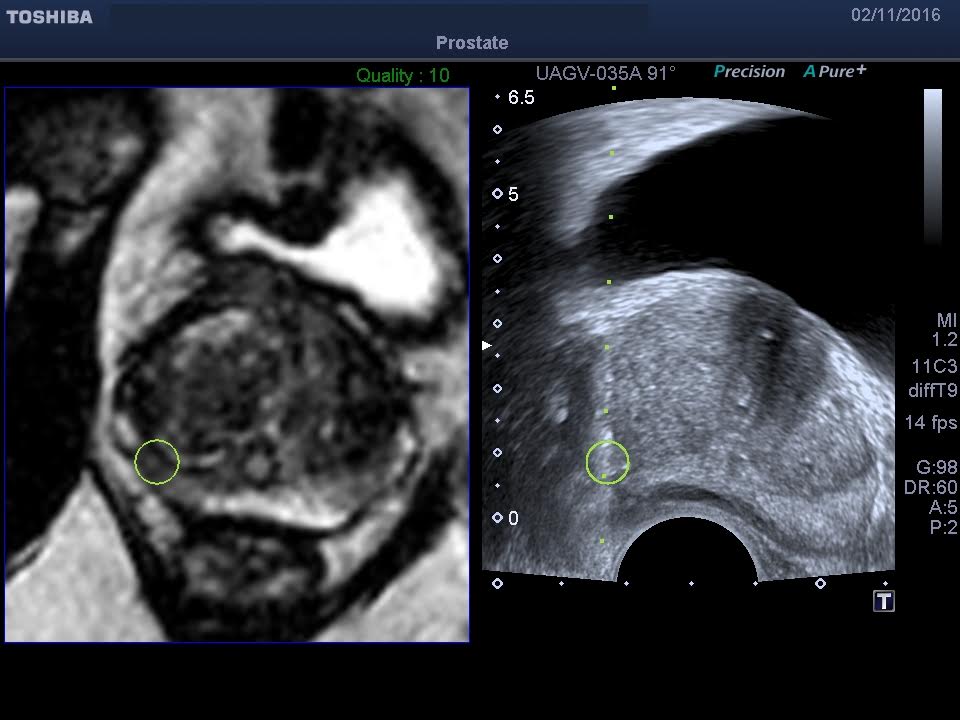

Una biopsia guiada por el sistema de ecografía Smart Fusion permite un nivel de precisión y seguridad mucho mayor que ningún otro procedimiento. Sincronizando imágenes previamente obtenidas de resonancia magnética o TAC con la imagen de ecografía en tiempo real podemos localizar las lesiones con total precisión evitando biopsias y agilizando los tiempos para la obtención de un diagnóstico.